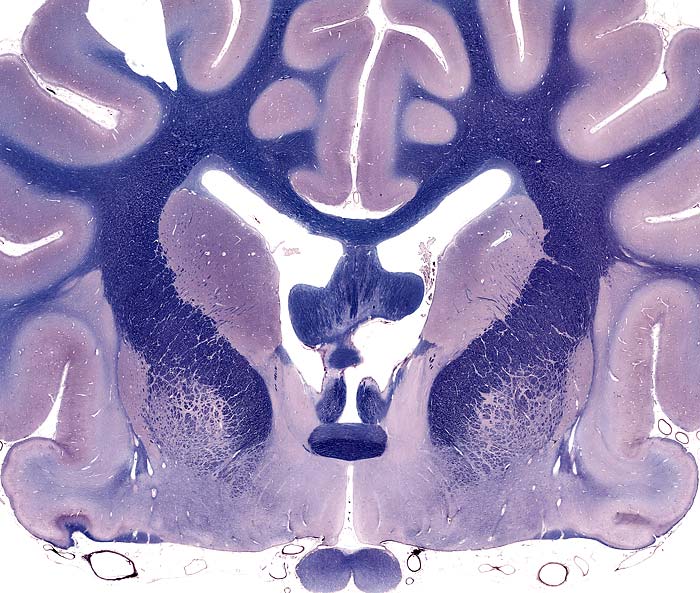

Telencephalon

Cerebral hemisphere

gray matter

cerebral cortex (neocortex)

basal nuclei:

nbsp; caudate nucleus

nbsp; putamen

globus pallidus

claustrum

white matter

cerebral white matter

corpus callosum

internal capsule

lamina terminalis

ventricles

lateral ventricle

interventricular foramen

Transection: Rostral Commissure and Corpus Striatum